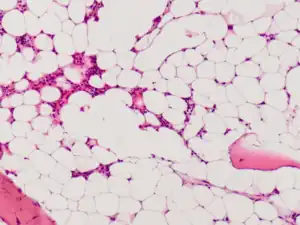

| Micrograph of bone marrow taken from a person with aplastic anemia. The bone marrow is mostly fat cells with few blood forming cells.[2] | |

The cause is unclear in 65% of cases.[3] Other cases may occur following a viral infections, due to a genetic conditions such as Fanconi anemia, or exposure to chemicals, medications or radiation.[3][4] The diagnosis may be suspected based on low blood cells together with low reticulocytes and the absence of changes concerning for blood cancer.[3] The diagnosis is confirmed by a bone marrow biopsy finding mostly fat cells instead of blood forming cells.[5]